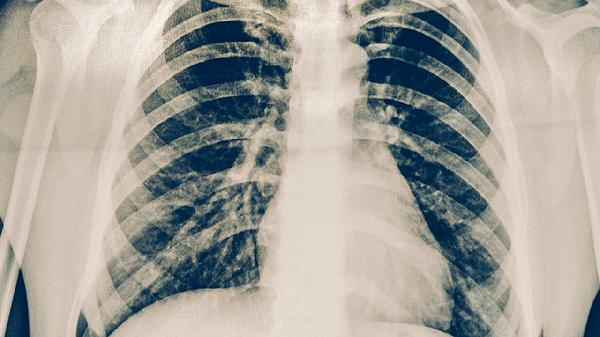

胸部X线检查能直观显示肺部病变情况,肺结核典型表现为上叶尖后段或下叶背段出现斑片状、结节状阴影,可能伴有空洞形成。该检查有助于评估病变范围和治疗效果,但不能单独作为确诊依据。对于疑似病例需定期复查观察病灶变化,活动性肺结核病灶通常呈现边缘模糊的浸润影,治愈后可遗留纤维钙化灶。